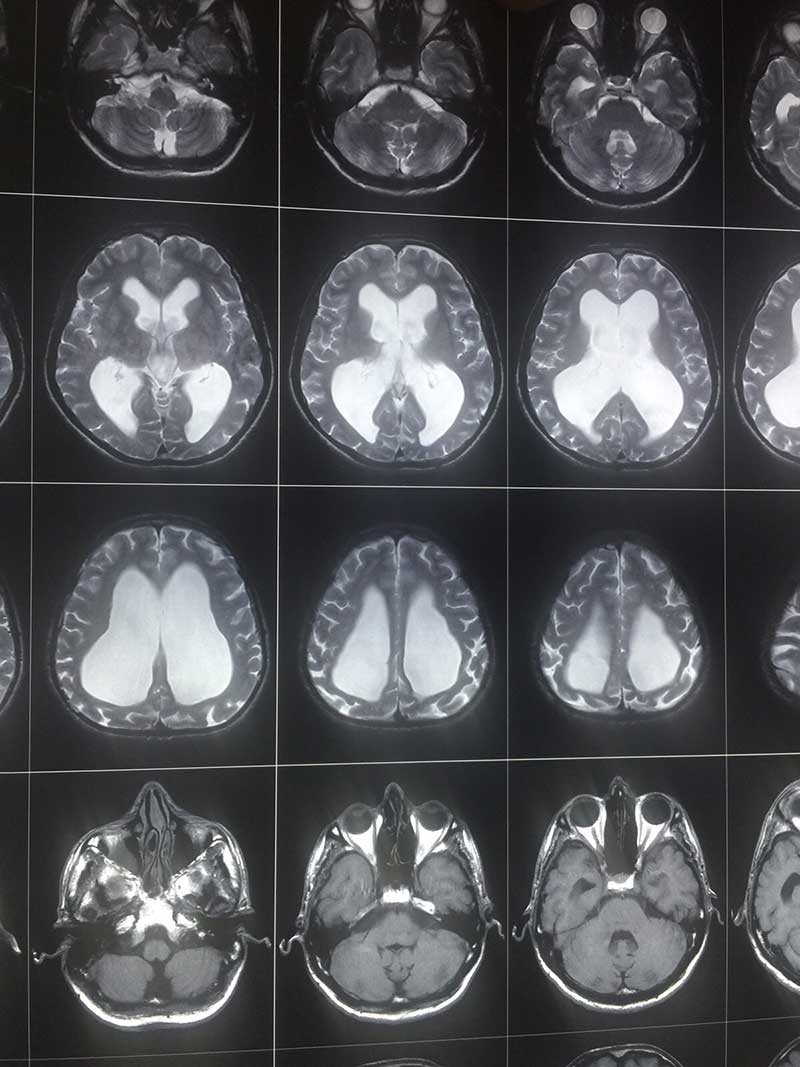

Arrested Hydro T2W

Arrested Hydro 3 Lat

Arrested Hydro 2